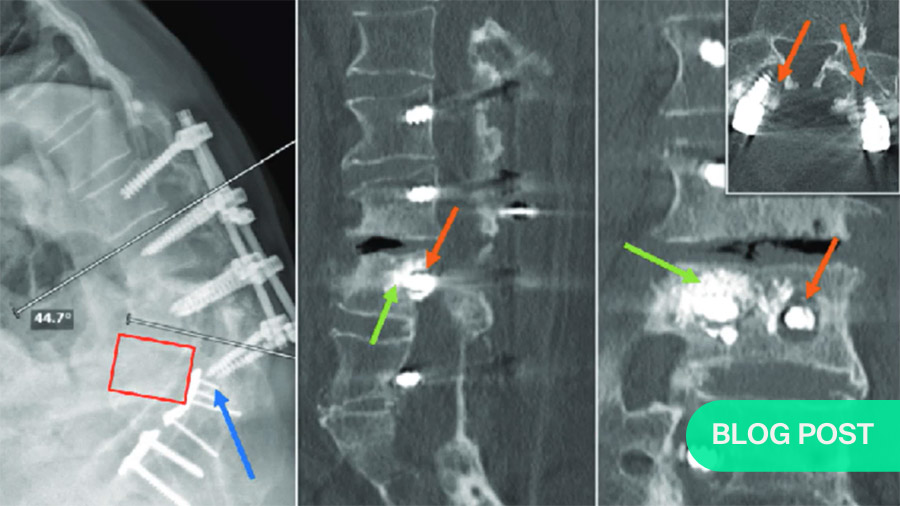

Use of fenestrated screws

Fenestrated screws are hollow, allowing a path through which to pump in cement. The object is not to fill the cavity behind the screw completely, but to form a ball of cement on the end of the screw. This greatly increases the area supporting the screw. If a kyphoplasty is indicated, the surgeon can insert a stent or balloon, fill it with cement, and screw into the cement.

Anterior stabilization is also commonly necessary.

For both vertebroplasty and kyphoplasty, which are posterior instrumentation solutions, it is often necessary to add anterior stabilization. For that, the surgeon removes the fractured vertebral body and places a stabilizer anteriorly to reconstruct the anterior column. Because of the characteristics of osteoporotic bone, this can only be used in addition to—not instead of—posterior instrumentation.

With all the benefits of strengthening the damaged area of the spine, it is also very important to remember that the vertebrae above the implant-strengthened section remain very vulnerable. As this often results in progressive kyphosis, particularly in the thoracic vertebrae, there is a significant risk of developing neurologic compromise. To guard against this, we can inject various amounts of cement into the at-risk vertebrae to distribute the stresses. In terms of fracture prevention, tapering the doses, i.e., 4ml, then 3ml then 2ml between successive vertebrae, has shown an excellent protective effect against fractures.